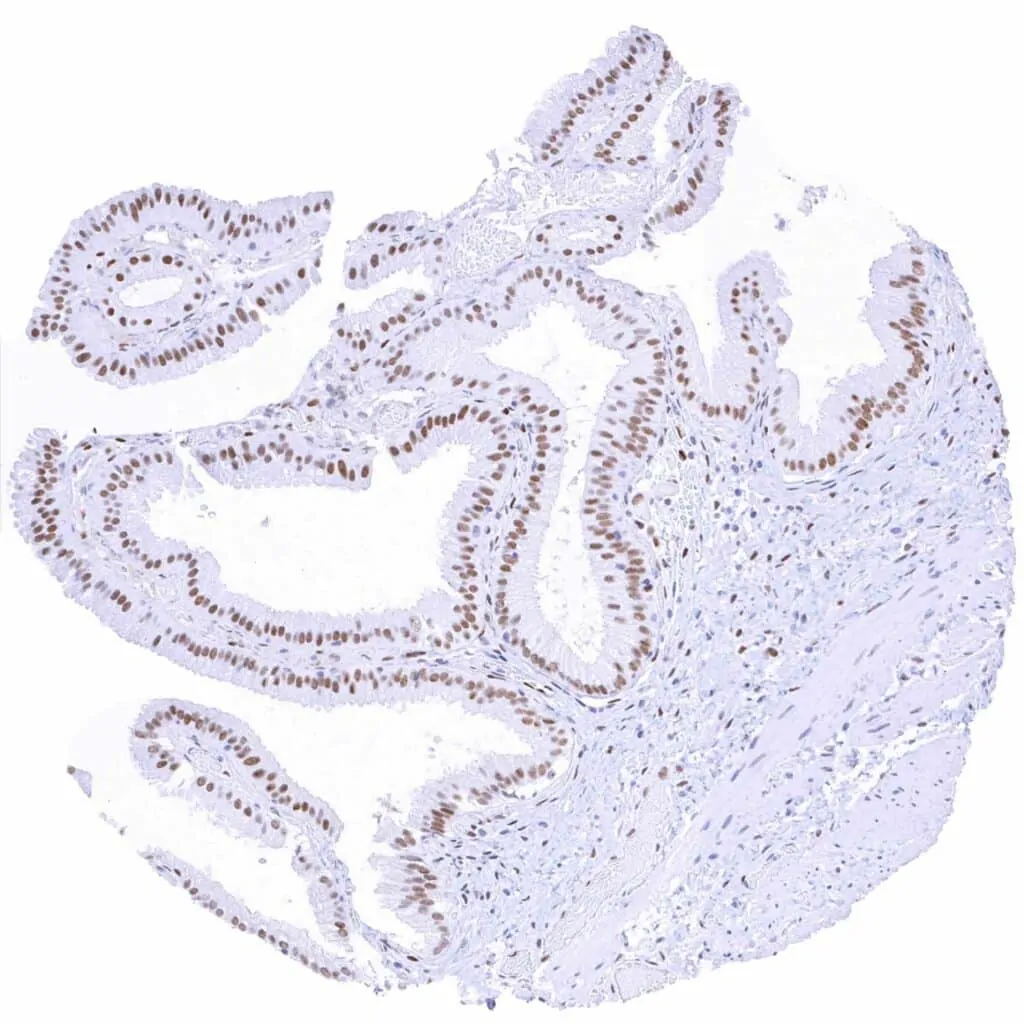

Appendix, mucosa – Weak to moderate TLE1 staining in epithelial cells. In this sample, staining is most intense at the surface and weaker in the crypts